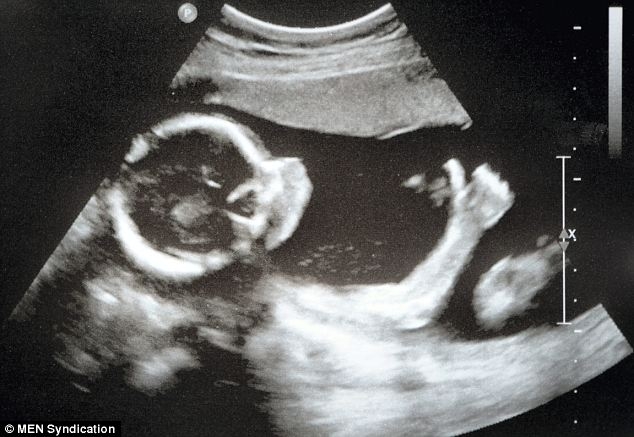

Итак, несколько раз спрашивала о хорошем узисте , среди которых девочки советовали Муминат , но я все мимо пропускала их советы , ходила к другим.

Сегодня я наконец пошла к Муминат по отзывам. Хотя настроена была скептически.....

Ииии... Я в восторге! УЗИ делала очень долго , при этом рассказывая о каждой мелочи! Параллельно все объясняла очень пон...